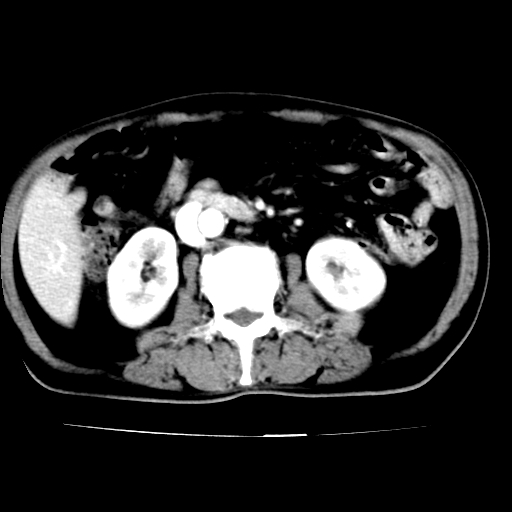

腹主动脉分叉处真性动脉瘤,附壁血栓形成。

给平扫片看看血管壁钙化情况。

此病例平扫图像已发,请大家看看!